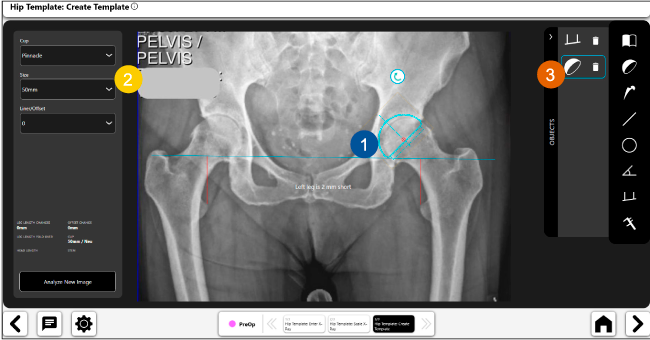

Planeación preoperatoria mediante la creación de plantillas digitales para reemplazo de cadera y análisis intraoperatorio

Disponibilidad de plantillas digitales de cadera.

Expediente histórico y personalizado, optimiza la planeación con el calendario de casos realizados en Velys TM y utiliza los íconos interactivos para una rápida revisión.

Anotaciones digitales y herramientas de análisis de longitud de pierna.